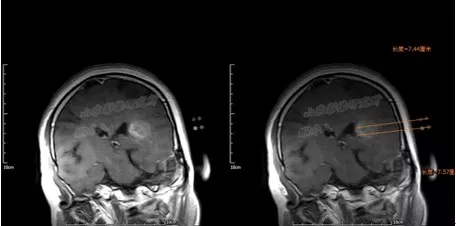

磁共振图清晰显示了满女士手术后复发病变情况

医生说,该病变在脑内位置较深,与周围组织关系复杂,手术完全切除难度较大。

术前TPS计划

山东省医学影像学研究所/磁共振微创介入科的李成利主任在了解满女士的病情后,采取了

磁共振联合个体化平行插植3D打印模板引导I125放射性粒子植入治疗。